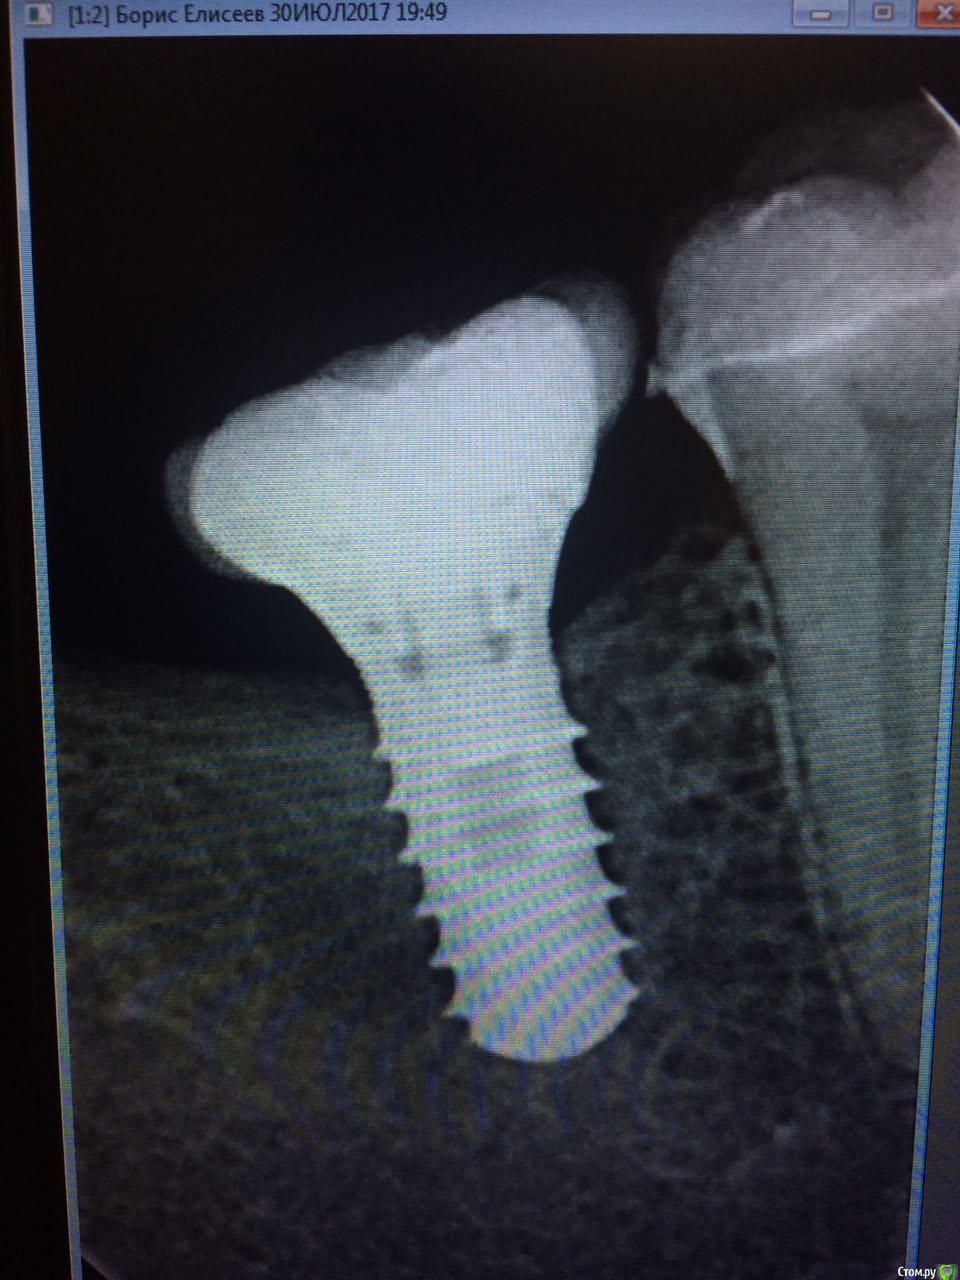

permico Опубликовано 23 августа, 2017 Поделиться Опубликовано 23 августа, 2017 (изменено) Добрый день.Примерно год назад во Франции мне были установлены 2 импланта на нижнюю челюсть взамен отсутствующих семерок (восьмерки были удалены еще раньше), т.е.37 и 47 зубов. Система Implant Direct (США), тип Swish plus, длина 10 мм. диаметр 5.7 и 4.1 мм. Врач уверил, что они являются репликой трансгингивальных Straumann Tissue Level с полированной шейкой и полностью совместимы. В общем, интегрировались они нормально, коронки он установил и я с ними проходил год без жалоб.Недавно сходил здесь в Москве к стоматологу, чтоб подкрутить винты на имплантах. Он все сделал и сказал, что нужно мне показаться хирургу-имплантологу так как они установлены скорее всего неправильно, забивается много пищи между коронками и десной (они сделаны с "балконом") и очень вероятно осложение в виде резорбции костной ткани. Сходил на консультацию к одному хирургу в Москве, он сказал, да действительно они неправильно установлены и им поможет только вынимайзинг с последующей установкой новых на то же место. Если сейчас не переустановлю, то через примерно пять лет их в любом случае придется вынимать, так как винт начнется оголяться, но уже кости будет меньше и будет труднее устанавливать новые.Хотел бы совета от специалистов на форуме, действительно ли они требуют удаления или можно сделать что-то другое. чтобы решить проблему.Прикладываю изображения (панорамный снимок после операции, недавние снимки имплантов, и фото их во рту, последние не очень хорошего качества, вечером могу попробовать переснять)Спасибо заранее, Борис Изменено 23 августа, 2017 пользователем permico Ссылка на комментарий

red_butler Опубликовано 23 августа, 2017 Поделиться Опубликовано 23 августа, 2017 показаний к удалению не увидел 9 Ссылка на комментарий

Art 7 Опубликовано 23 августа, 2017 Поделиться Опубликовано 23 августа, 2017 если хотите продлить жизнь имплантатам то надо выкрутить коронки, сделать пластику десны вокруг имплантатов и переделать коронки. это даст много лет жизни ималантатам 5 Ссылка на комментарий

Bier Опубликовано 23 августа, 2017 Поделиться Опубликовано 23 августа, 2017 понаблюдайте пока так. Чистите получше. Сейчас показаний к удалению нет. 1 Ссылка на комментарий